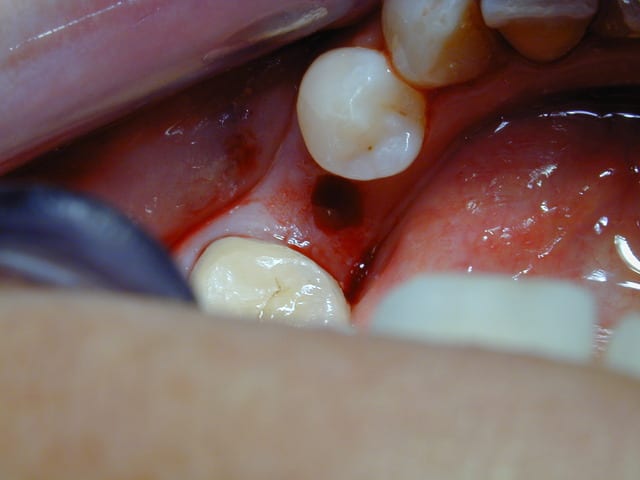

ça fait quand même vis à bois ....

12